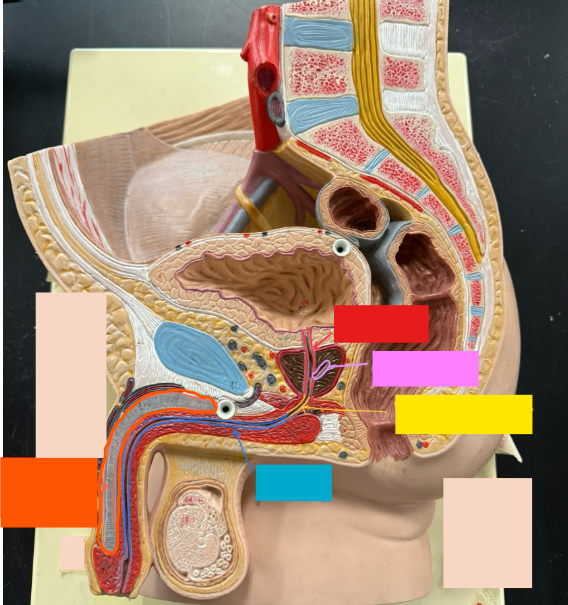

What is the name of the red box?

Ureter

What is the name of the red box?

Vas deferens

What is the name of the yellow box?

Seminal vesicle

What is the name of the blue box?

Prostate

What is the name of the light blue box?

Prepuce

What is the name of the blue box?

Corpus spongiosum

What is the name of the black box? X2

Prostate

What is the name of the purple box?

Rectum

What is the name of the yellow box?

Anus

What is the name of the red box?

Prostatic urethra

What is the name of the pink box?

Ejaculatory duct

What is the name of the yellow box?

Membranous urethra